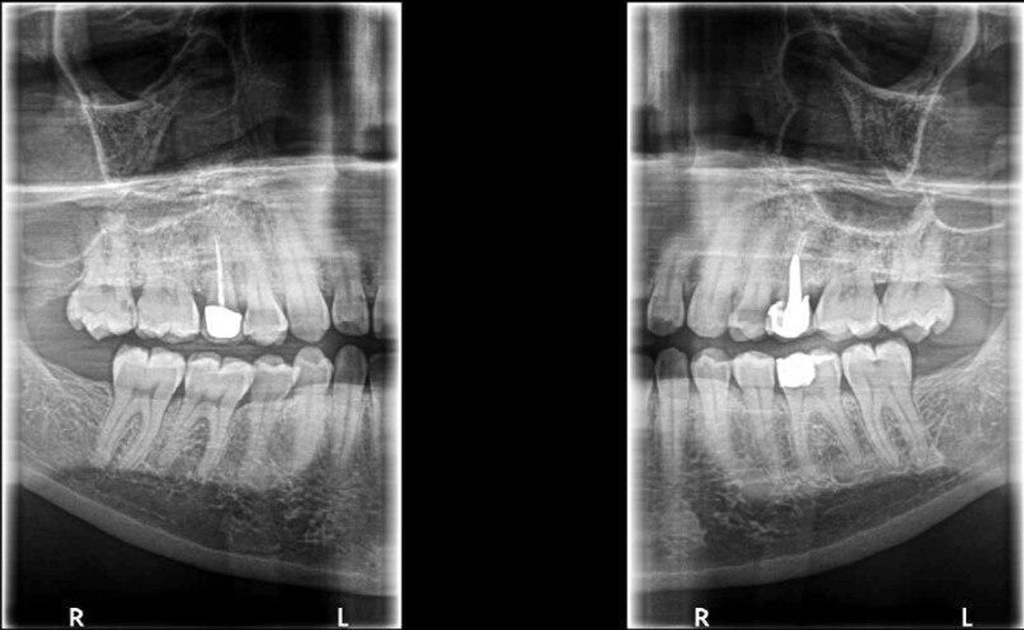

This next-gen model expands your field of view options for unparalleled flexibility. With nine selectable views ranging from 4x4 cm all the way up to 12x10 cm, the CS 8200 is equipped to cover virtually any diagnostic need your practice requires.

The CS 8200 3D blends 2D panoramic technology, CBCT imaging and 3D model scanning to create one powerful unit.

The CS 8200 3D offers multiple fields of view, to support all of your diagnostic needs — from routine exams to specialized ones.

This all-in-one unit is designed to seamlessly capture stunning 2D panoramic views and medium field of view 3D cone beam scans with ease. With a wide range of medium to large field of view settings from 4x4 cm up to 12x10 cm, the CS 8200 supports an impressive variety of specialized dental applications.

Whether you need detailed bitewing analysis, full jaw visualization, or targeted higher resolution imaging, this system's adaptable field of view has you covered. And as your practice grows, simply upgrade to add cephalometric capabilities for even greater clinical flexibility.